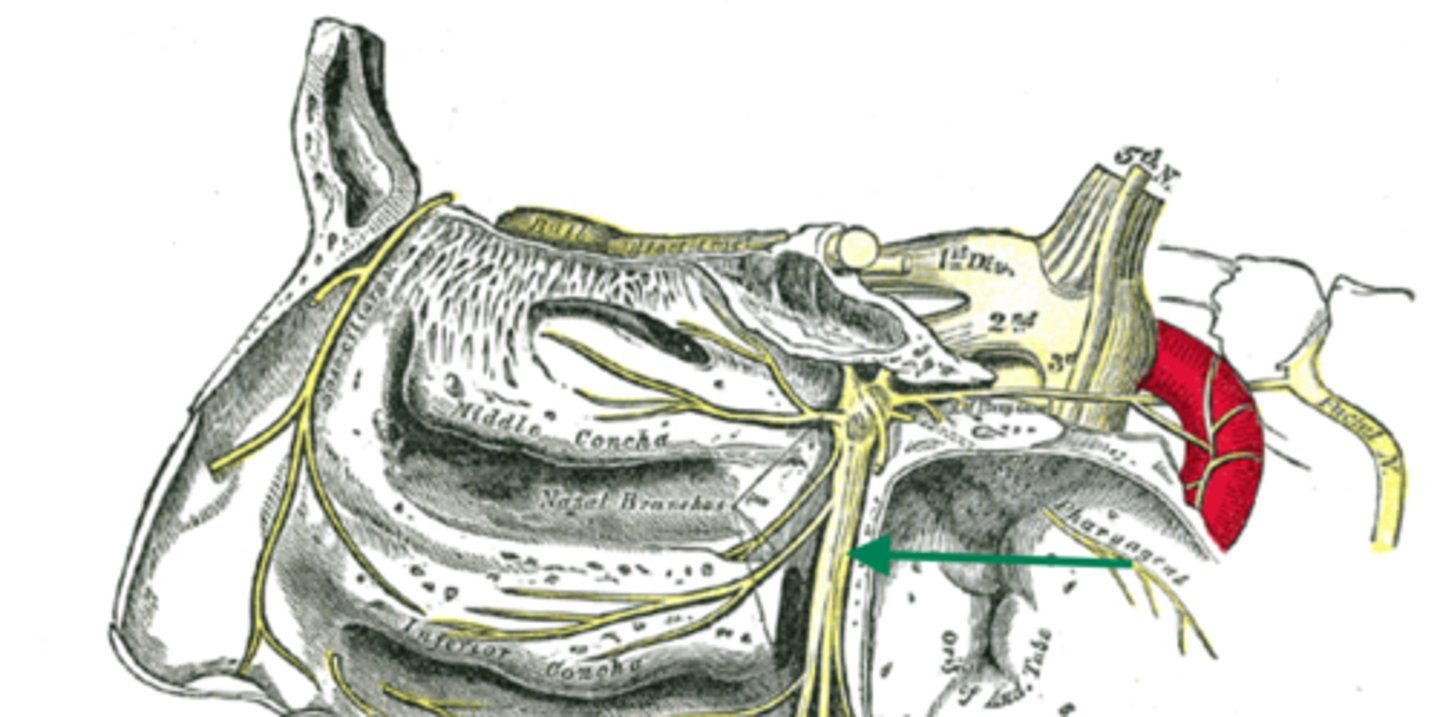

cribriform plate

sphenoidal sinus

pharyngeal tonsil

tonus tubaris

opening of pharyngotympanic tube

salpingopharyngeal fold

superior meatus

middle meatus

inferior meatus

inferior nasal concha

uvula

frontal sinus

nasal septum

hard palate

nasopalatine nerve

descending palatine artery

greater palatine nerve

greater palatine artery

greater palatine foramen

lesser palatine nerve

lesser palatine artery